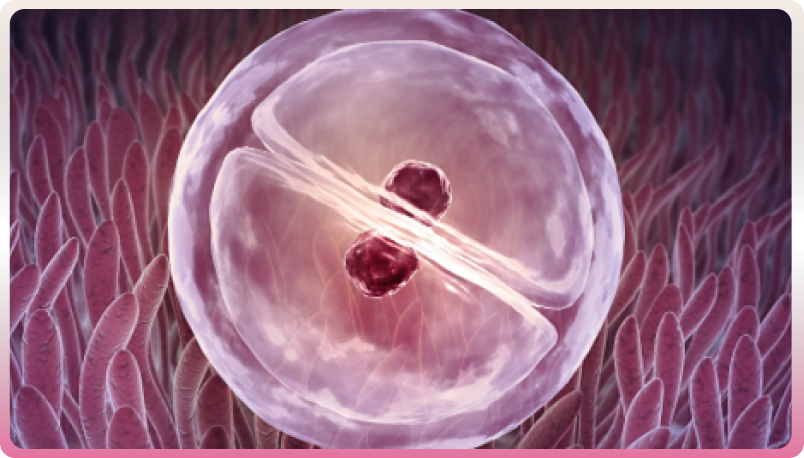

-Fécondation du sperme et de l'ovule

Enfin, la quatrième étape est la fécondation in vitro. Le sperme est traité afin de recueillir les spermatozoïdes les plus fécondants. Les ovocytes et les spermatozoïdes sont placés dans un milieu de culture favorable à leur survie et déposés dans l’incubateur à 37 degrés.

Transfert d'embryon dans l'utérus

Deux à six jours après l’incubation, l’œuf fécondé devient un embryon qui peut être transféré dans l’utérus. On obtient plusieurs embryons. Le nombre d’embryons transférés dépend de l’âge de la femme et des stratégies de prise en charge propres aux centres de PMA. Il a diminué au cours des dernières années pour réduire le nombre des grossesses multiples et les complications maternelles et fœtales associées.